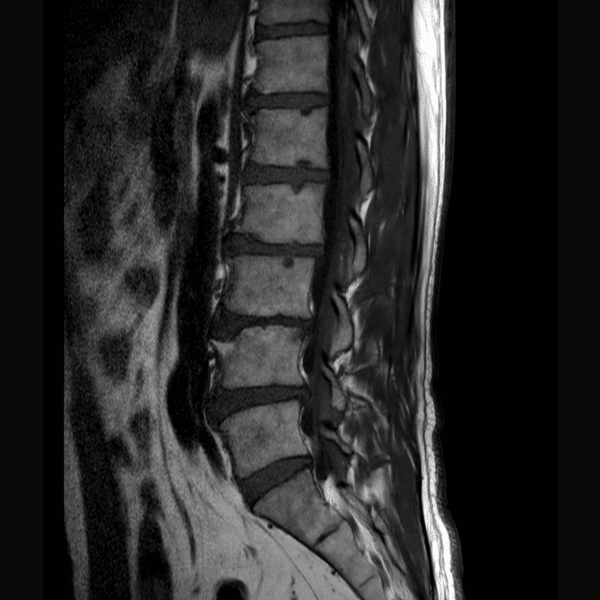

L-Spine T2WI

1.5T Siemens MAGNETOM Essenza

2D TSE

(L) 0.6×0.8×4.0 mm

(R) 0.6×0.8×4.0 mm

Conventional SwiftMR™ 03:00 01:28 (51% Faster)